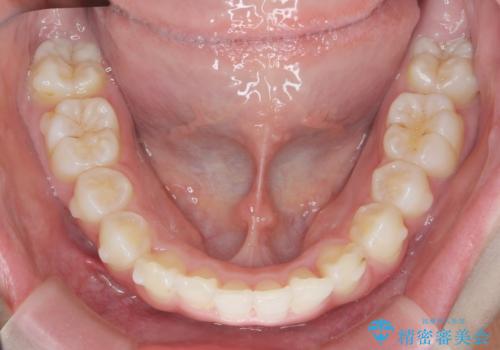

サクソフォン(アルト)の演奏で崩れてしまった歯並び、マウスピース矯正治療

- 高校時代の吹奏楽の部活でサクソフォン(アルト)を担当、「一生懸命練習をしすぎて気づいたら歯並びが悪くなっていた。矯正治療を受けたい!。」

とマウスピース矯正を希望され来院されました。

歯列の乱れが大きく難易度が高いため、

・治療期間の長期化が予想されること

・マウスピースで治り切らない場合ワイヤー矯正に変更すること

をご理解いただいた上でマウスピース矯正治療を計画します。

口腔内の清掃状態の良さに加えて、マウスピースを毎日きっちりと装着し、しっかりと使用していただけたことからワイヤー矯正は行わずにきれいに歯並びを治すことができました。

途中顎位が変わり、マイクロインプラントを併用した上顎臼歯の遠心移動が必要となったため治療が長期化しました。